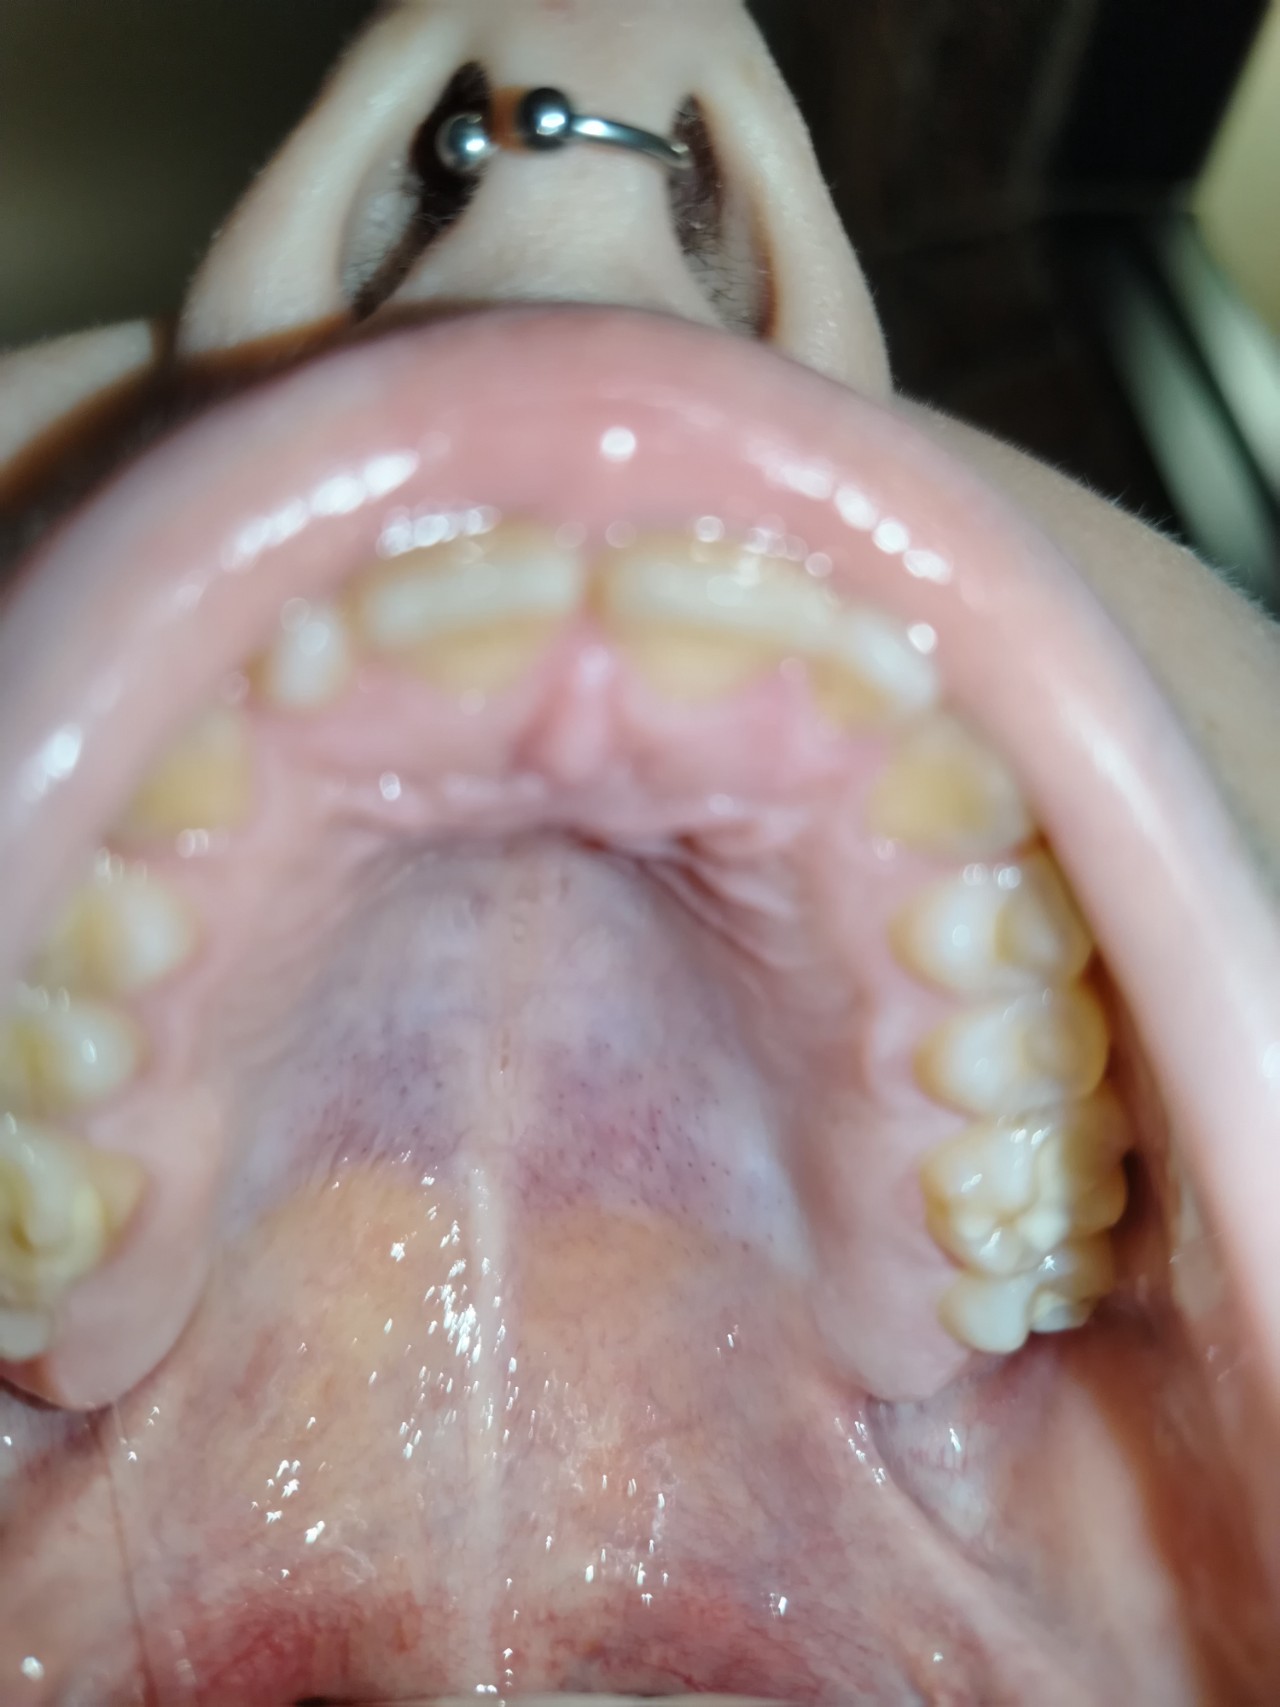

Здравствуйте, сегодня утром столкнулась с проблемой, что при употреблении пищи небо стало фиолетовым, а позже появились красные пятна, ощущение жжения и сдавливания на небе. Если не ем, то оно перестаёт болеть, как только начинаю, опять по новой, что это может быть?